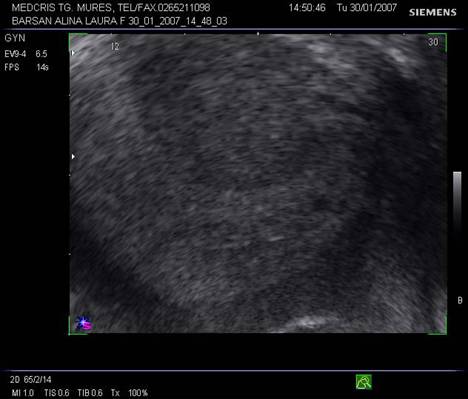

Fig nr 53 Aceeasi sarcina extrauterina ca in figura precedenta, se evidentiaza coroana trofoblastica la ecoul doppler color si se schiteaza vezicula vitelina ( cu sageata )